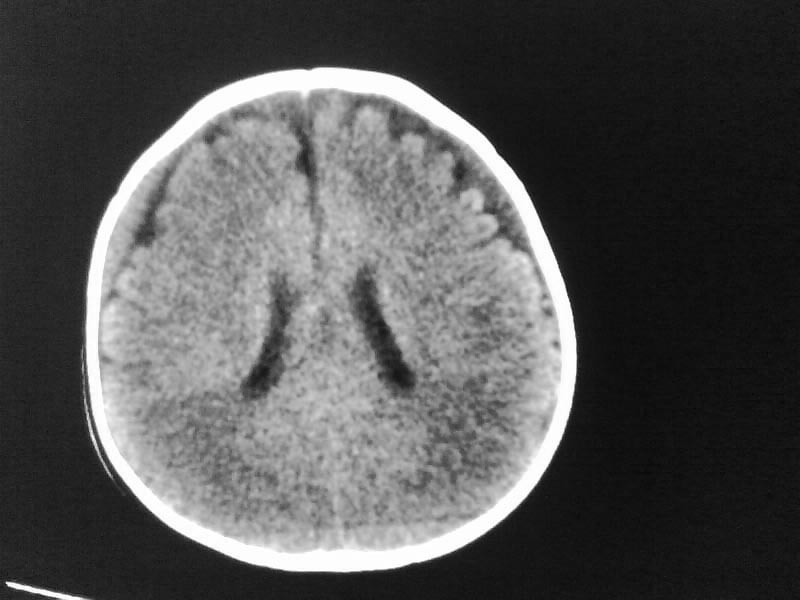

以下是引用小初学者在2009-4-15 10:26:00的发言:[br]考虑右侧额顶部硬膜下血肿。

以下是引用随光逐影在2009-4-15 17:59:00的发言:[br]1)右侧额颞顶部硬膜下血肿。2)外部性脑积水。